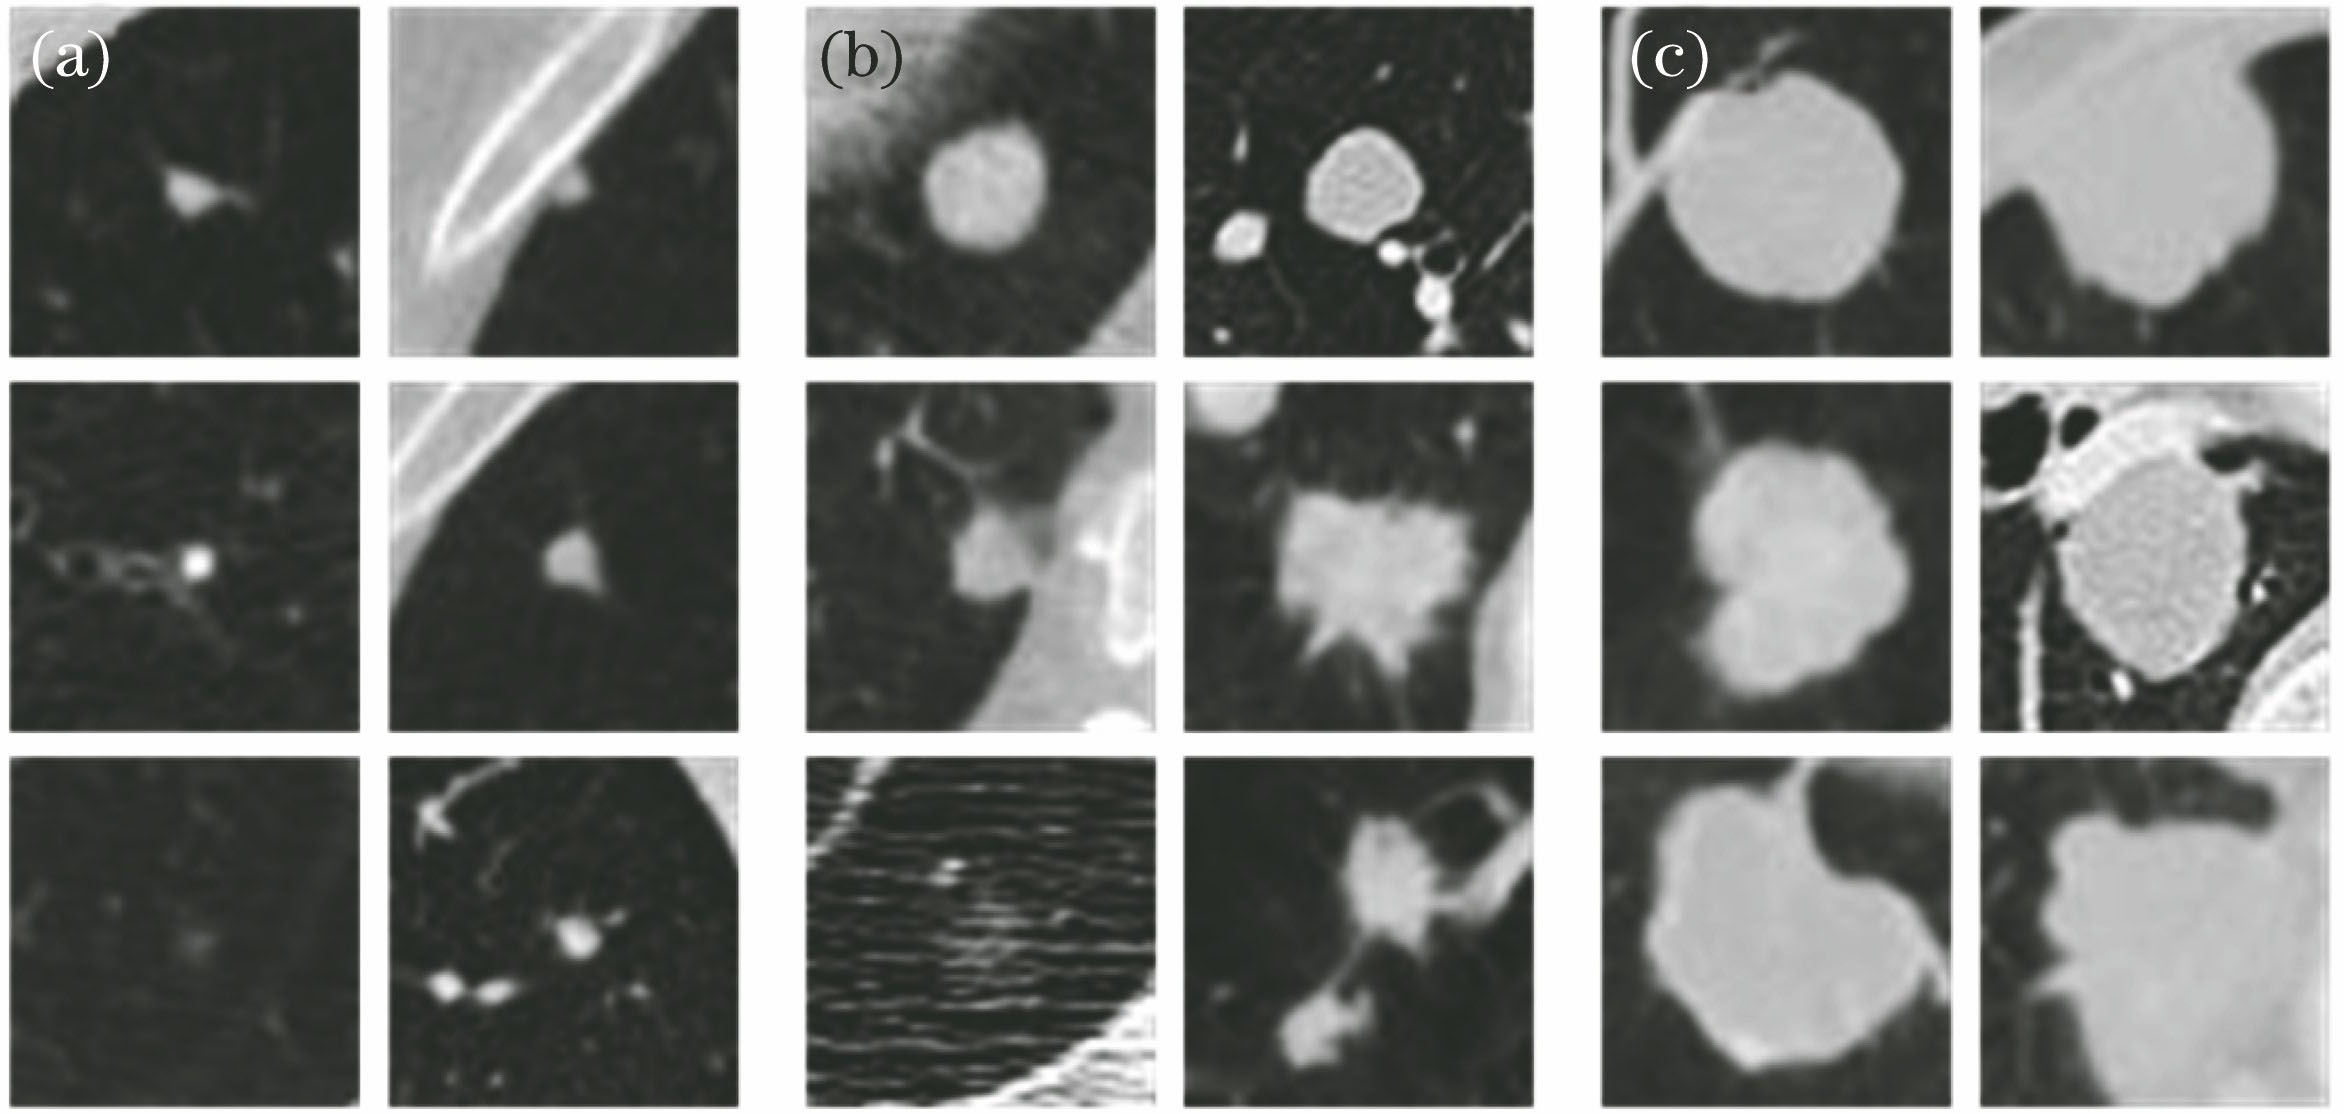

图 5. 数据库中不同尺寸结节的图像。(a)小结节;(b)中等结节;(c)大结节

Fig. 5. Images of nodules with different sizes in the database. (a) Small nodules; (b) middle nodules; (c) big nodules